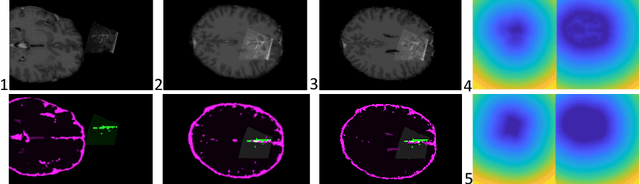

Abstract:Intra-operative ultrasound is an increasingly important imaging modality in neurosurgery. However, manual interaction with imaging data during the procedures, for example to select landmarks or perform segmentation, is difficult and can be time consuming. Yet, as registration to other imaging modalities is required in most cases, some annotation is necessary. We propose a segmentation method based on DeepVNet and specifically evaluate the integration of pre-training with simulated ultrasound sweeps to improve automatic segmentation and enable a fully automatic initialization of registration. In this view, we show that despite training on coarse and incomplete semi-automatic annotations, our approach is able to capture the desired superficial structures such as \textit{sulci}, the \textit{cerebellar tentorium}, and the \textit{falx cerebri}. We perform a five-fold cross-validation on the publicly available RESECT dataset. Trained on the dataset alone, we report a Dice and Jaccard coefficient of $0.45 \pm 0.09$ and $0.30 \pm 0.07$ respectively, as well as an average distance of $0.78 \pm 0.36~mm$. With the suggested pre-training, we computed a Dice and Jaccard coefficient of $0.47 \pm 0.10$ and $0.31 \pm 0.08$, and an average distance of $0.71 \pm 0.38~mm$. The qualitative evaluation suggest that with pre-training the network can learn to generalize better and provide refined and more complete segmentations in comparison to incomplete annotations provided as input.